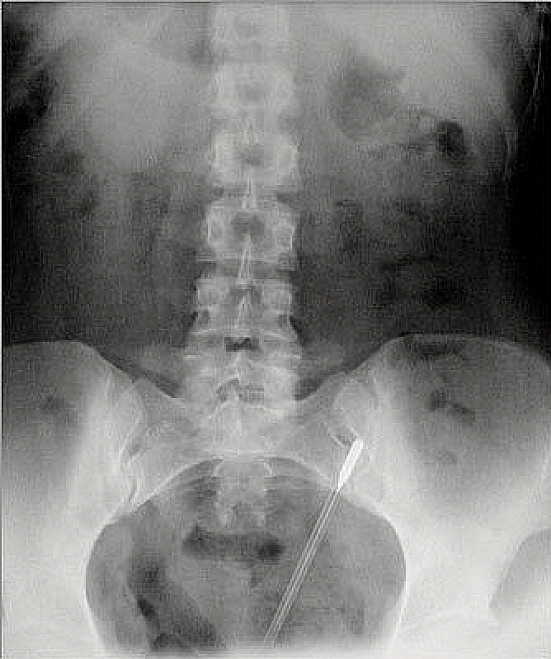

A thermometer

Apparently, this guy was a bit too excited to check his temperature.